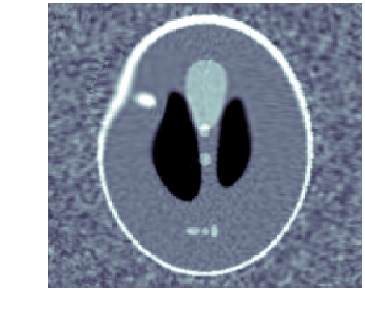

When template has correct topology and intensity levels, then \acLDDMM-based indirect registration with geometric group action is remarkably stable as shown in [9]. Using a geometric group action, however, makes it impossible to create or remove intensity, e.g., it is not possible to start out from a template with a single isolated structure and deform it to a image with two isolated structures. This severely limits the usefulness of \acLDDMM-based indirect registration, e.g., spatiotemporal images (moves) are likely to involve changes in both geometry (objects appear or disappear) and intensity. See fig. 1 for an example of how wrong intensity influences the registration.

We clearly see that metamorphosis based indirect registration can handle a template with wrong intensities. As a comparison, see fig. 1(c) for the corresponding \acLDDMM based indirect registration using the same template and data. Furthermore, the different trajectories also provides easy visual interpretation of the influence of geometric and intensity deformations.